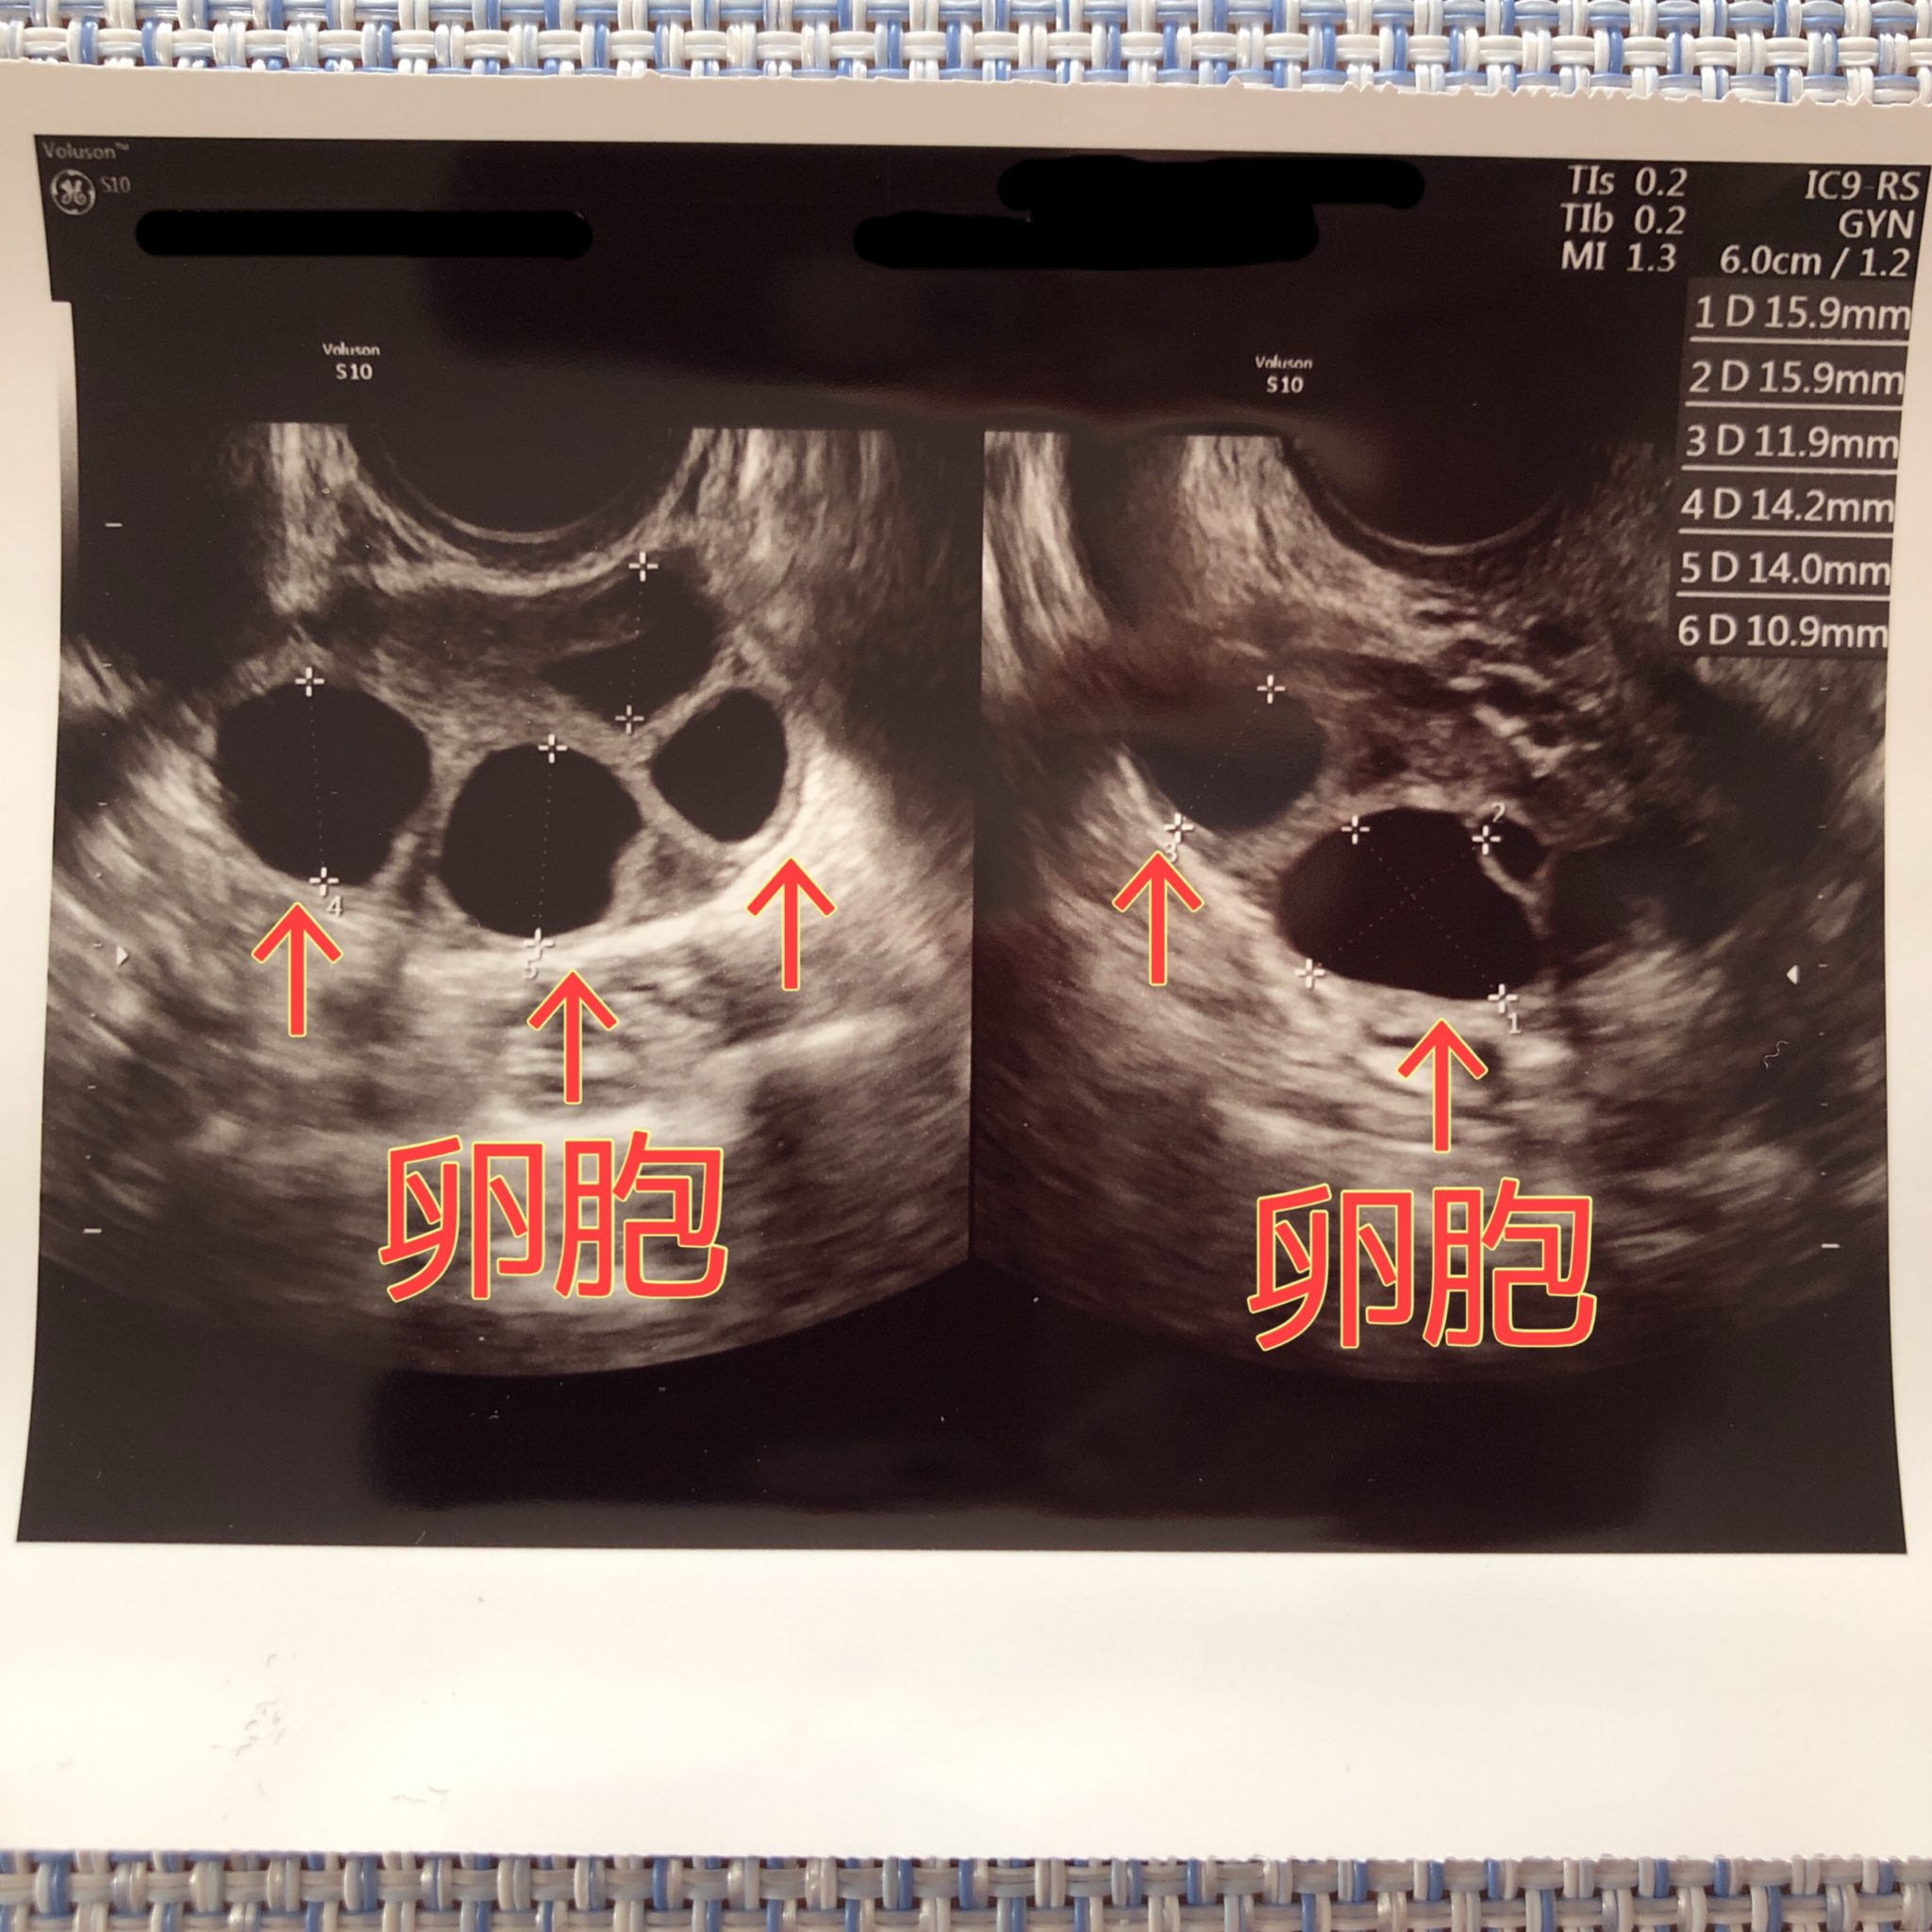

多嚢胞性卵巣症候群〜普段の生活で気をつけること 産婦人科専門医による妊活ガイド

多嚢胞性卵巣症候群(PCOS)でお悩みの方へ 大津市 医療法人 木下レディースクリニック